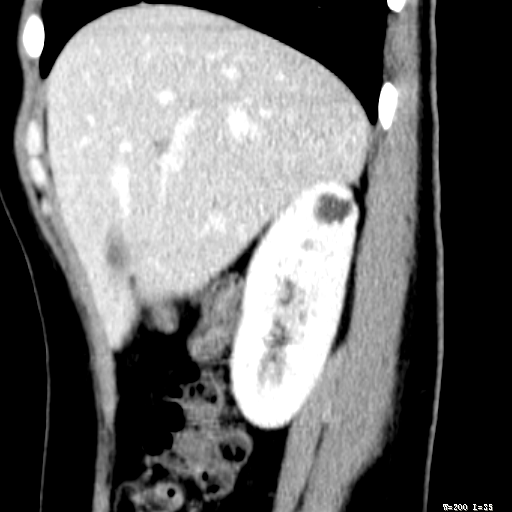

标题: CT25345:右肾占位。 [打印本页]

标题: CT25345:右肾占位。

女,30岁,右腰部胀痛3个月。

增强无明显强化,先考虑血管平滑肌脂肪瘤,建议作薄层扫描右mri检查,

增强无明显强化,先考虑血管平滑肌脂肪瘤,建议作薄层扫描右mri检查

考虑右肾近上极囊肿;建议必时行mri检查。